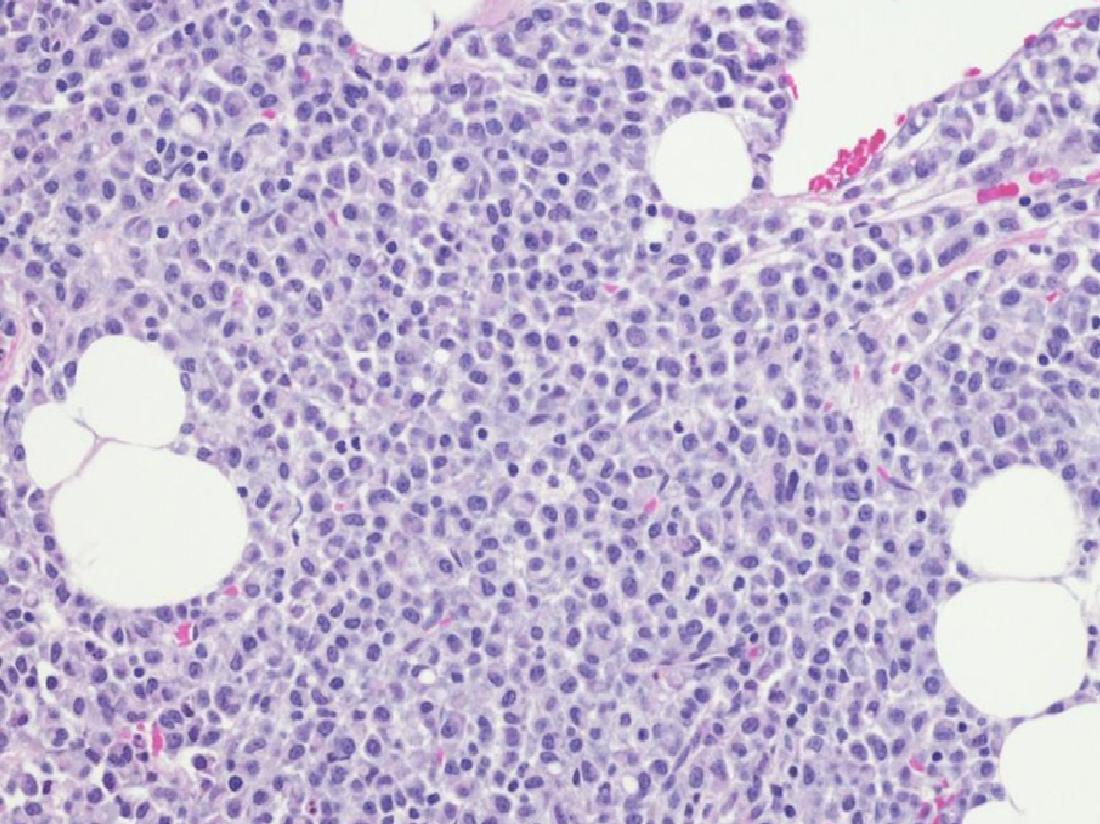

• Kan pıhtılaşmasına yardımcı olan trombositler (pıhtılaşma hücreleri=kan pulcukları) yer alır. Kemik iliğinin normal görünümü Resim 1’de verilmiştir.

Resim 1: Kemik iliği dokusundan alınan biyopsinin mikroskop altındaki görünümü